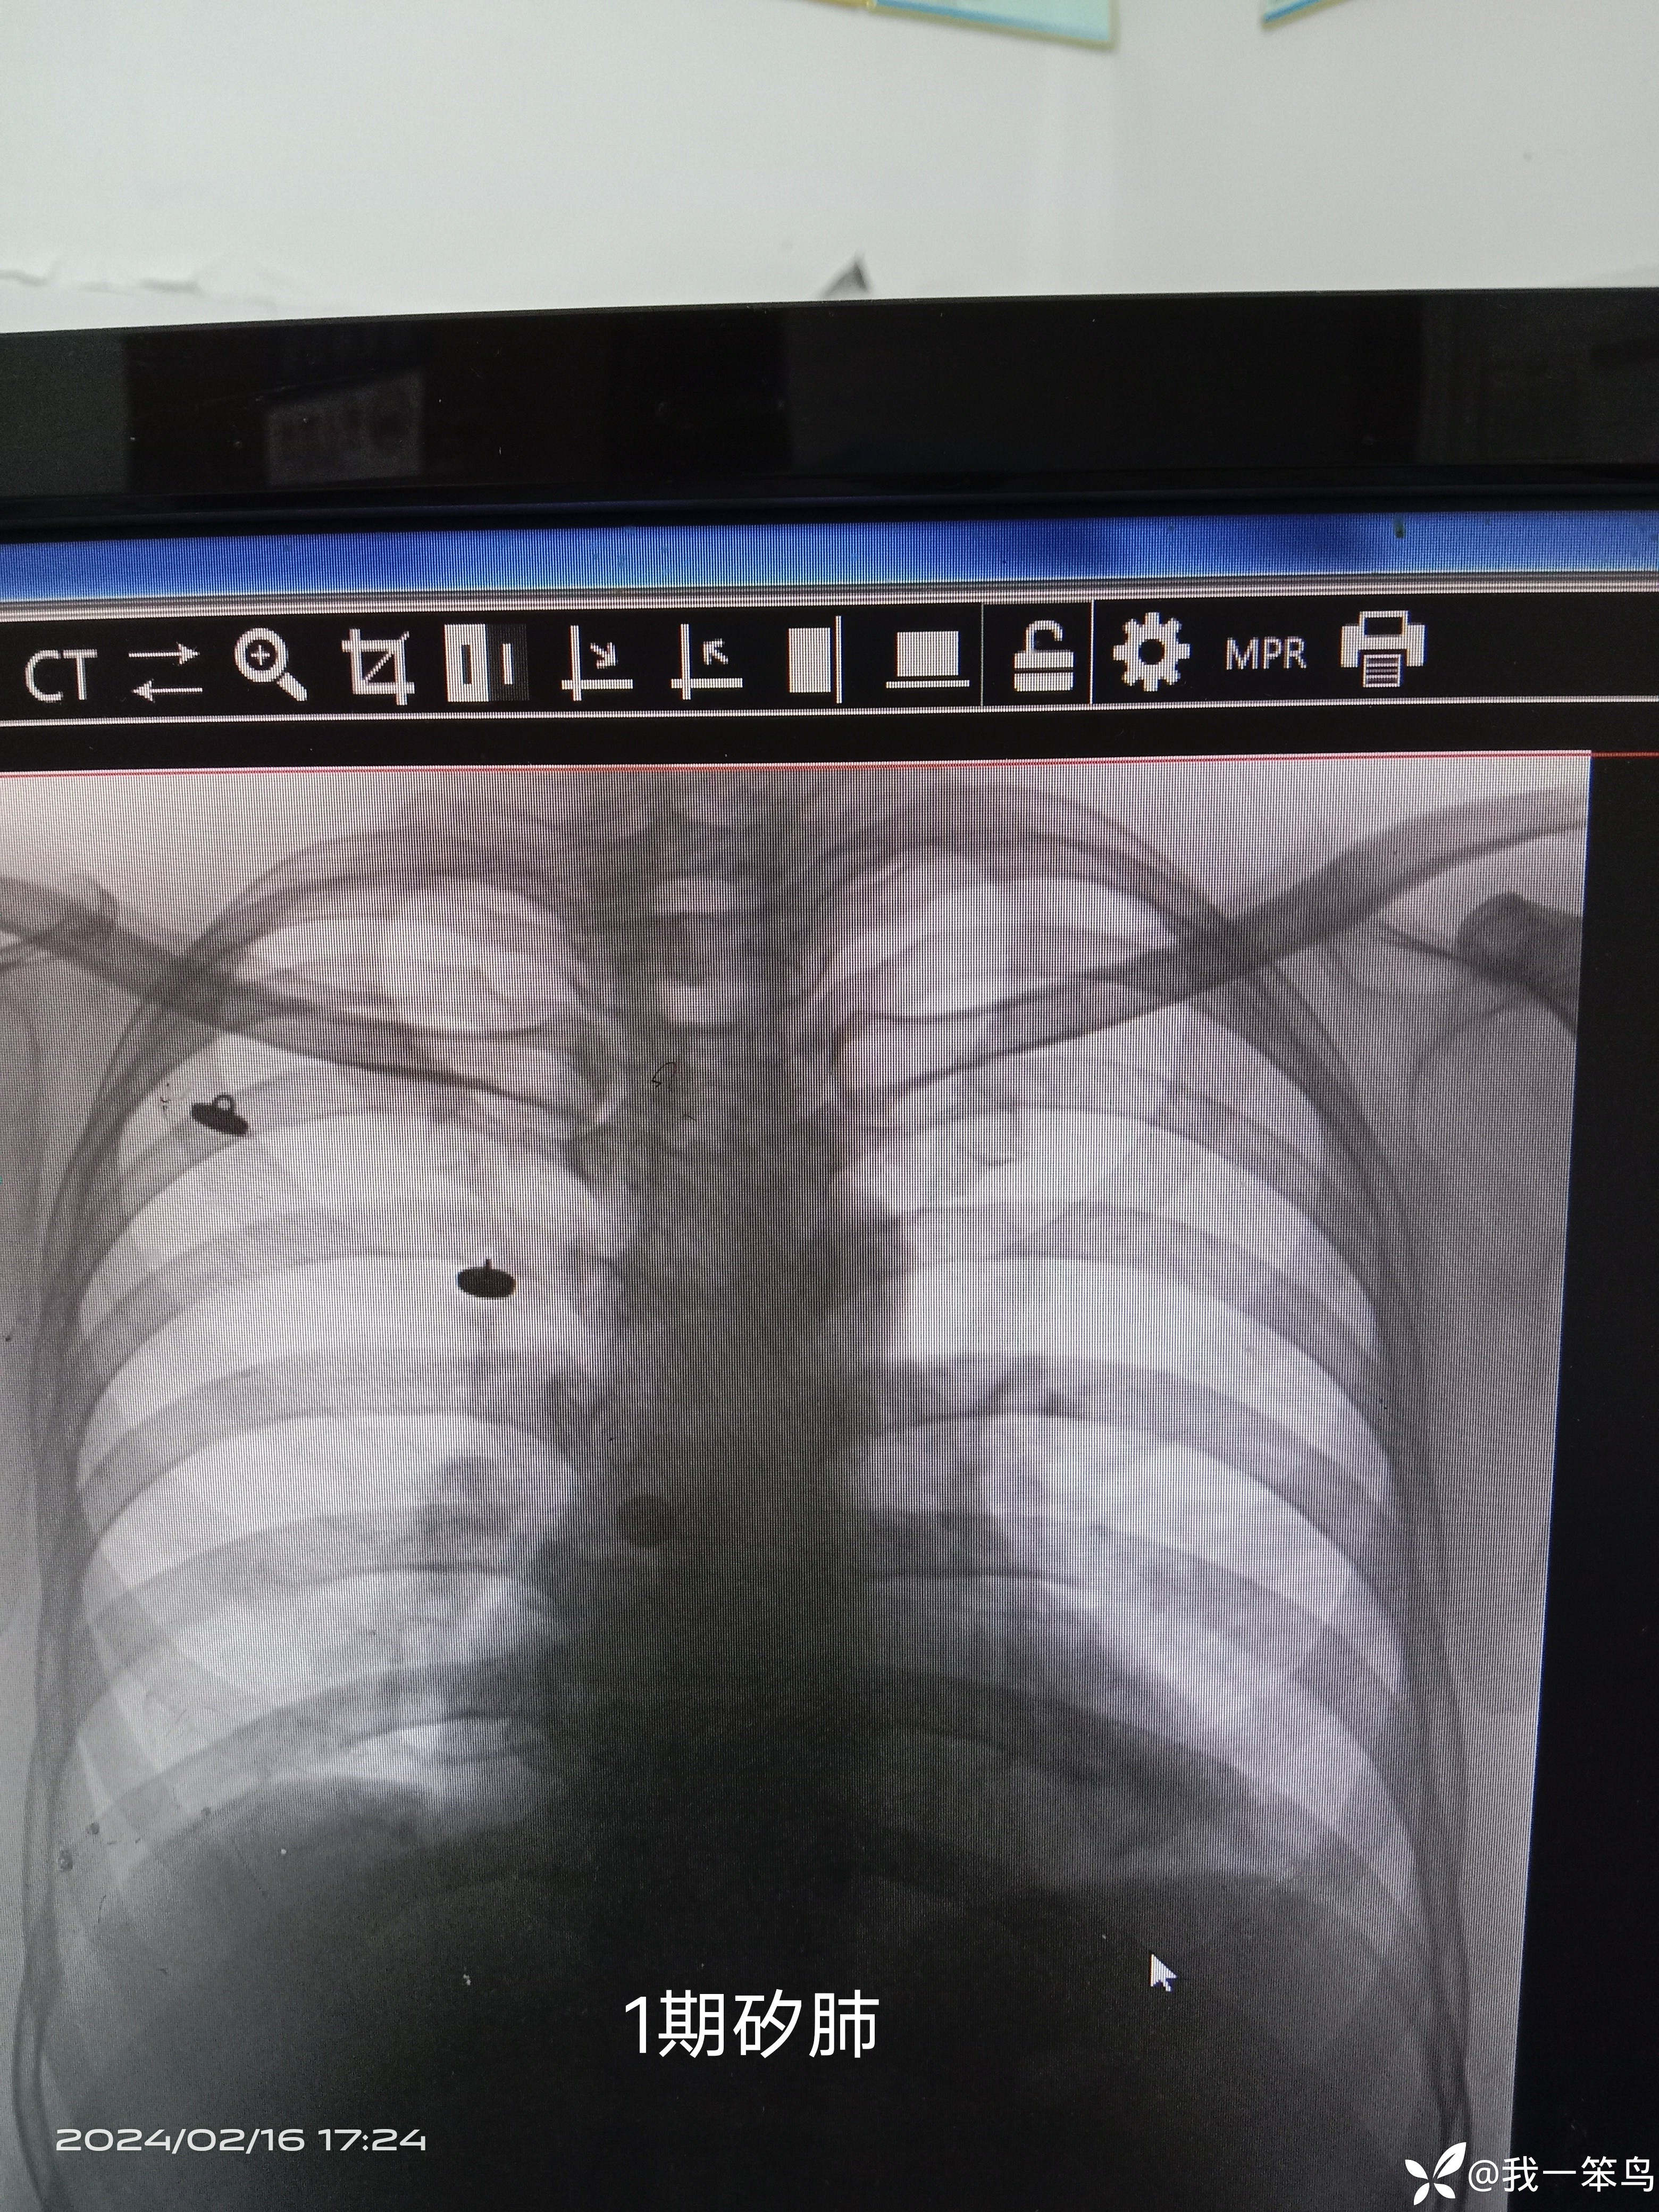

主诉:反复咳嗽、咳痰间断血痰11年,加重伴胸闷,气促、咯血10天

现病史: 患者既往从事煤矿井下工作多年,于11年前开始出现咳嗽.咳痰,剧烈时痰中血丝症状,并逐渐加重伴活动后胸闷、胸痛、气促,2010被矽肺鉴定小组确诊为“Ⅰ期矽肺”,曾多次在省职业病防治院住院治疗,予以肺灌洗,抗肺纤维化、润肺化痰、提高免疫力及对症支持治疗后,好转出院。此次发病于10多天前,患者不慎受凉后再次出现咳嗽咳痰,阵发性,咳白色粘稠痰,量多,间断性咳血,伴活动后气促、胸闷、胸痛,无畏寒、发热,无恶心、呕吐症状,自行在家口服药物治疗(具体用药不详),疗效欠佳,遂来我院就诊,以“Ⅰ期矽肺并肺部感染”收入住院治疗。此次发病以来,患者食欲精神可,大小便正常。

拟诊:1.Ⅰ期矽肺;2.咳血查因:a继发性肺结核?b肝功能异常?C血小板减少症?d血液病?3..冠心病,心脏扩大,心绞痛型,心功能2级。